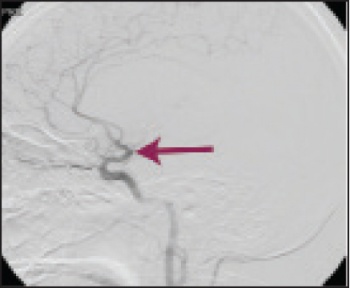

See Figures 1(i)-3(ii) for images of a successful endovascular therapy case.